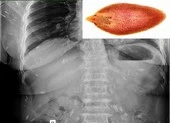

Cụ thể, bệnh nhân Huỳnh Thị T. (64 tuổi, trú huyện Đại Lộc, tỉnh Quảng Nam) nhập viện trong tình trạng đau bụng, sốt rét run 39 độ C, đau hạ sườn phải, nôn ra dịch.

Qua thăm khám và chụp CT-Scan ổ bụng, các bác sĩ phát hiện bệnh nhân bị sỏi ống mật chủ - nhiễm trùng đường mật, chỉ định nội soi mật tụy ngược dòng lấy sỏi (ERCP) ngày 2-11.

Bệnh nhân thời điểm điều trị tại Bệnh viện Đà Nẵng. Ảnh: BVCC

Tiến hành nội soi ngược dòng, các bác sĩ phát hiện sán lá gan lớn trong ống mật chủ của bệnh nhân. Sau can thiệp ERCP, các bác sĩ gắp được hai con sán lá gan lớn còn sống (dài 30 mm, ngang 10 mm) ra khỏi cơ thể bệnh nhân.

Bệnh nhân tiếp tục dùng thuốc điều trị đặc hiệu để diệt trứng sán còn tiềm ẩn trong người. Sau nội soi can thiệp, bệnh nhân hồi phục, tỉnh táo, hết nôn, hết đau hạ sườn phải.

Theo bác sĩ Nguyễn Xuân Tuấn, Khoa Nội tiêu hóa, Bệnh viện Đà Nẵng, sán lá gan lớn ở trong ống mật chủ rất hiếm gặp, đặc biệt là còn sống. Việt Nam từng ghi nhận hai trường hợp có sán lá gan lớn trong ống mật chủ tại Thừa Thiên Huế (2012) và Đồng Nai (2018), được lấy bằng phương pháp phẫu thuật.

Đây là trường hợp đầu tiên tại Bệnh viện Đà Nẵng và được bắt qua nội soi mật tụy ngược dòng.